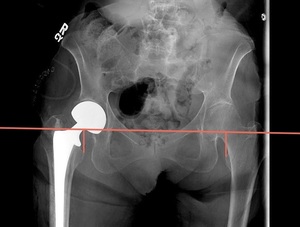

Multiple surgical approaches have been described for hip hemiarthroplasty (HHA) in the setting of a displaced femoral neck fracture.9 The direct anterior approach utilizes the intermuscular and internervous plane between the sartorius (i.e., hip flexor in the anterior thigh innervated by the femoral nerve) and tensor fascia latae (i.e., hip abductor innervated by the superior gluteal nerve) superficially, and the rectus femoris (i.e., hip flexor and knee extensor in the anterior thigh innervated by the femoral nerve) and gluteus medius (i.e., hip abductor innervated by the superior gluteal nerve) for the deep layer.10 This approach is typically performed in the supine position, which allows the use of intraoperative fluoroscopy, and in our study, a grid to measure and assess implant positioning, monitoring for leg length discrepancies (LLD) and femoral offset (FO) (Figure 1a). In contrast, the anterolateral approach utilizes the intermuscular plane between the tensor fascia latae and gluteus medius. The patient is positioned on a non-radiolucent peg board in the lateral position, which does not allow for utilization of a fluoroscopic grid.

At our institution, both surgeons each have their own technique, which has remained unchanged over the last eight years. One surgeon, using the GF technique, performs a supine, direct anterior approach with intraoperative fluoroscopic imaging utilizing a grid to view the internal components and to estimate the leg length and offset compared to the contralateral extremity (Figure 1a). The other surgeon, using the IE technique, uses an anterolateral approach with no intraoperative imaging. In order to reestablish neck length, the surgeon judges the length by visualizing and attempting to replace the amount of bone that was removed above the lesser trochanter (i.e., a bony anatomic landmark located near the hip). To restore offset, a manual intraoperative abductor shuck test is performed. For this test, the size of the femoral head is measured and used as a guide for the trial size for testing. After the hip hemiarthroplasty trial is reduced, soft tissue tension is manually assessed. Next, the surgeon applies a distracting force with a bone hook around the neck of the implant to check for overall fit and suction within the acetabulum (i.e., the socket of the hipbone where the head of the femur fits) (Figure 2). The soft tissue tensioning of the surrounding hip musculature is judged by whether the abductor musculature can be repaired without excessive tensioning. Leg length is again reassessed intra-operatively by comparing the medial malleoli (i.e., the inner side of the ankle) and patella (i.e., the small bone located in the front of the knee joint) of each leg.